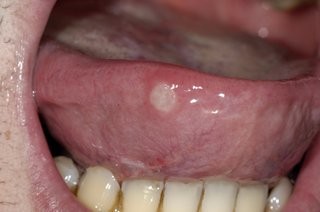

Why you should never ignore a mouth ulcer that won´t heal

Are you prone to getting mouth ulcers? There are a number of different contributing factors and presentations of mouth ulcers; and thankfully most are harmless and heal on their own. However, there are some that can appear very similar but are in fact far more serious. If your mouth ulcer isn’t healing, we recommend you visit us immediately to assess the possibility of mouth cancer. Any mouth ulcer that has been present for more than three weeks must be treated as serious until proven otherwise.

A mouth ulcer, otherwise known as a canker sore or an aphthous ulcer, occurs when there is a break in the skin of the mouth (mucosal lining), exposing the underlying connective tissue. It may have a 'crater-like' appearance and is often red and painful, similar to a blister in the mouth.

Aphthous ulcers are the most common type of mouth sore, and are generally the result of some kind of trauma and/or reduced immune response. These sores typically heal in a week or two, but they can recur throughout the person's lifetime. 'Major' aphthous ulcers are greater than 1 cm in diameter and take much longer to heal. Common mouth ulcer causes that we see include:

Unlike the relatively benign examples mentioned above, oral cancers may initially show up as a mouth ulcer. Oral cancer can present itself in many ways: some people first become aware of an ulcer that won't heal: these lesions are usually a painless mouth ulcer, but it doesn't come and go the way other mouth ulcers do. Any mouth ulcer that has been present for more than three weeks must be treated as serious until proven otherwise. Similarly, if you have developed a red , white or mixed red and white patch, you must urgently seek a professional opinion.

What are the stats for oral cancer?

If you look at the statistics, about 50% of people with oral cancer die from their disease even after extensive surgery and radiotherapy. While small oral cancers that are detected early have a 80-90% cure rate, many oral cancer sufferers don't see an expert until it is at an advanced stage.

Canker Sores

These mouth ulcers are painful and unpleasant, but they are nothing to worry about. This common problem goes away on its own in around a week, and during this time they aren’t contagious. Research does point to stress being a cause, if you find yourself getting them regularly.

Oral Cancer

Often starting as a white patch, growth, or ulcer on the tongue that grows steadily, oral cancer is a serious condition that is most often seen in people who smoke or drink alcohol in larger quantities.